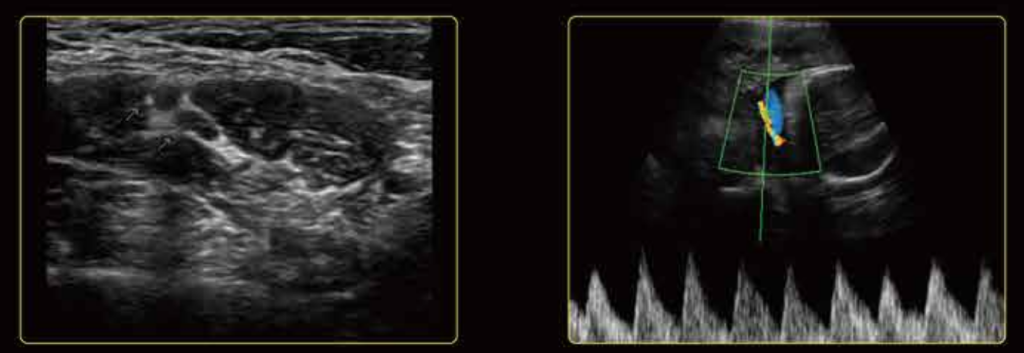

Шикарное качество изображения

U60 обеспечивает отличную детализацию, контрастное разрешение и равномерное изображение без ущерба для глубины проникновения. Превосходная цветопередача и чувствительность Допплера легко обнаруживают небольшие сосуды с низким кровотоком. Сонная артерия и правая печеночная вена

Митральный клапан и сосуды почек Плечевое нервное сплетение и пупочная артерия

Плечевое нервное сплетение и пупочная артерияПередняя панель U60